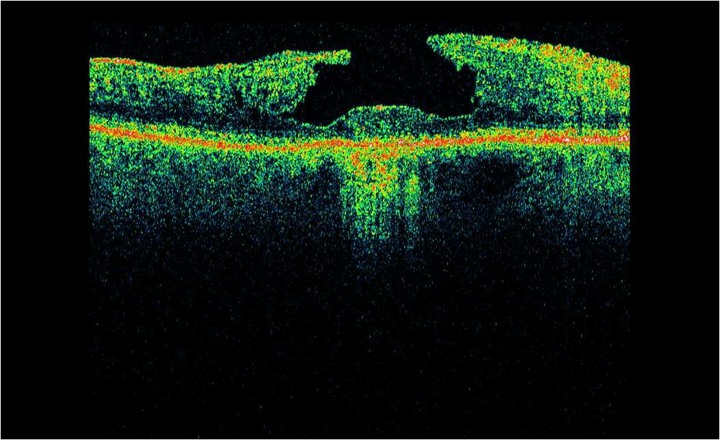

Optical Coherence Tomography uses low intensity infra-red light to give a 3D image of the back of the eye.  It shows not only the surface but also the depth of the structures.  It is similar to using ultrasound and creates an image not unlike an MRI or CT scan.

A 3D section of the layers ofthe retina and vitreous jellyA 3D section of the layers of the retina and vitreous jellyAge-related Macular Degeneration Dry FormAge-related Macular Degeneration Dry FormAge-related Macular Degeneration Wet FormAge-related Macular Degeneration Wet FormThe vitreous (jelly) pulling on the retinaThe vitreous (jelly) pulling on the retinaImage of Retina (back of the eye)Image of Retina (back of the eye)